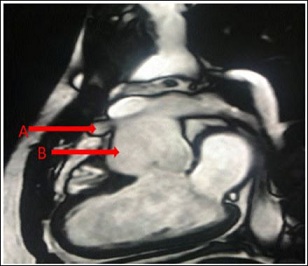

The chest pain was atypical in nature without any significant exertional dyspnea or syncope. He denied tobacco use but had been vaping for 4 years prior to presentation. On examination, vitals were stable. Auscultation of heart revealed a normal S1 and S2 without murmurs. The rest of the physical exam was within normal limits. Electrocardiogram showed sinus rhythm. Echocardiogram showed levocardia with normal ventricular systolic function and ejection fraction of 57%. Contrast computed tomography scan of the chest showed a 1.1x1.5x1.1 cm aneurysm of the proximal LAD artery (Figure 1). Findings were confirmed on Magnetic Resonance Imaging (Figure 2). Exercise myocardial perfusion imaging was also normal. The patient’s Adult Congenital Heart Disease Anatomical and Physiological classification was IIIA. Patient’s medical records were obtained and showed his LAD artery aneurysm diagnosis was madeaboutfiveyearsearlieratage13, and there was no interval progression since. After a multidisciplinary discussion, continued medical management was felt to be the best option for the patient with serial clinical follow-ups. On a 6-month follow-up, the patient continues to be doing well and has excellent functional capacity.

Figure 2: MRI showing A) Aneurysm of the proximal left anterior descending artery.B) Dilated aortic